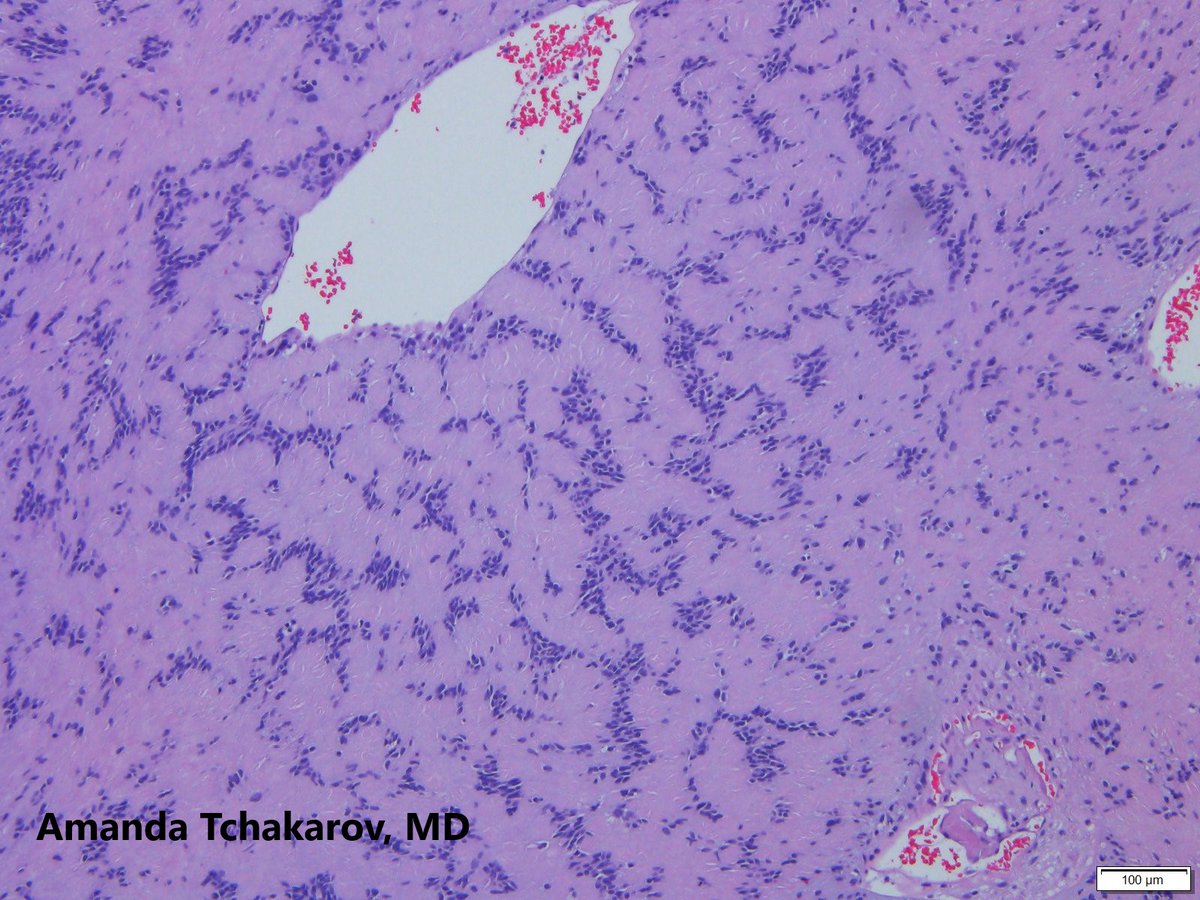

@ATchakarov1

A Tchakarov

10 months

Usually when I get a renal biopsy for proteinuria in a diabetic patient, it ends up being diabetic nephropathy...but sometimes there's something else going on. 👀🔬 #RenalPath #Nephropath #Nephrology #PathX #PathTwitter